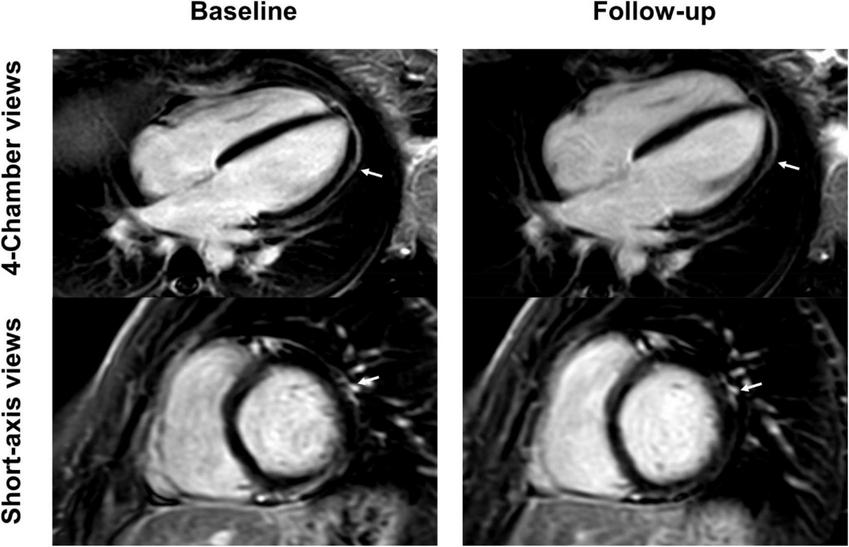

FIGURE 4

Short-axis and 4-chamber late gadolinium enhancement (LGE) views in a 26-year-old, previously healthy female after receiving the first dose of the Pfizer/BioNTech vaccine. Nearly complete resolution of LGE (arrows) at follow-up 2 months later with minor enhancement discernable at the apical lateral segment. Clinical correlation showed a complete resolution of previous symptoms which included chest pain and exertional dyspnea.